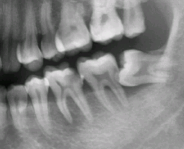

步驟二:局部粘膜消毒4%阿替卡因局部浸潤麻醉,探及3根管,拔髓不成形,少量出血,手用銼疏通根管至20#,測根長,根管預備。沖洗、蕩洗、乾燥根管封藥,暫封。

步驟三:沖洗、蕩洗、乾燥根管,試主尖片,達根長,蕩洗,拭淨,熱牙膠根充,墊底,暫封。

步驟四:基牙預備,精修。制取矽橡膠印模,矽橡膠咬合記錄。

治療後